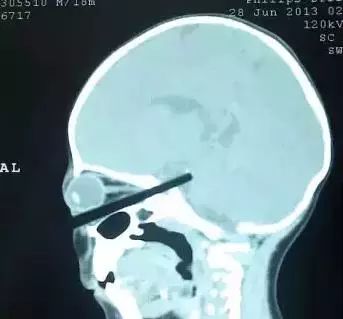

妈妈接电话 筷子插进一岁宝宝头内!

广州的一位刘女士,抱着自己一岁零三个月的宝宝喂饭,这个时候自己的手机响了,于是放 下孩子出去接电话,没想到刚说两句,屋内便传来孩子撕心裂肺的哭声……

刘女士放下手中的电话,急忙跑进屋内,眼前的一幕让她惊呆了,一根筷子直直的戳入孩子眼睛。

刘女士立刻冲上去将筷子拔掉,抱着儿子赶快到医院治疗。经过抢救,孩子在昏迷了整整八天之后醒了过来,但语言智力等方面也因此受到了严重的影响。

在这里提醒一下各位家长,如果孩子被异物伤到,要第一时间就诊,千万不要擅自拔出异物,以免造成第二次伤害。

一名上海男孩,2岁多,因为帮助爷爷递镙丝刀,不慎跌跤,镙丝刀从眼眶插入颅内;